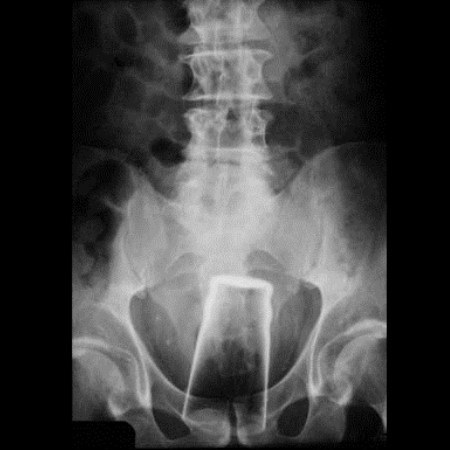

9. Ένα ποτήρι